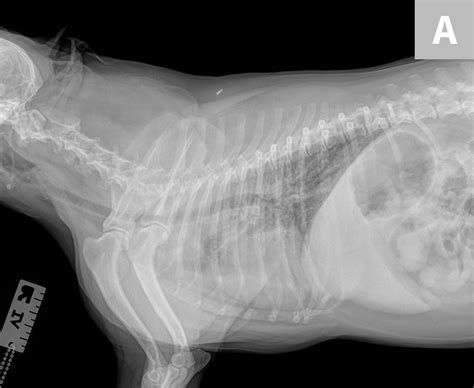

Dog Pneumonia Vs Lung Cancer : 2.5 year old Great Pyrenees : Additional allergy triggers or allergens come from sources other than the animal's skin.. Breathing.his lungs, but no spots.throwing.antibiotics. Since cough, shortness of breathe, wheezing , and fatigue are common symptoms of both diseases, it is possible to misdiagnose pneumonia at first. It takes more lives each year than the next three combined (colon, pancreatic, and breast), but it doesn't get a. It is also possible that a cancer diagnosis can be delayed if the cancer is mistaken for pneumonia. Pneumonia is a lung infection that leads to breathing difficulties and fluid in the lungs.

Some severely affected dogs may have extreme exercise intolerance. Read on and learn more about the symptoms, causes, and treatment of pneumonia in dogs. 32 years experience medical oncology. Plenty of detail in first. Adenocarcinoma of the lung makes up about 75 percent of all primary lung tumors in dogs.

Hank has lung cancer - Doberman Forum : Doberman Breed Dog ... from www.dobermantalk.com The prognosis of lung cancer in a dog really depends on the type of cancer your dog has developed and the extent of its spread throughout the rest of your dog's body. Lung cancer is the leading cause of cancer death in men and women in the united states. But in some rare cases, it may be a lung cancer (primary or secondary). Lung cancer is a general term that includes all abnormal lung tissue cells that multiply unregulated and form tumors or growths in the lungs. There are many possible causes. Malignant tumors trigger inflammation in surrounding normal lung tissue, and they may obstruct your airways and interfere with normal airflow. Lung cancer is actually the number one killer when it comes to cancers. Dog pneumonia or lung cancer.

It's tough hearing a diagnosis of metastatic pulmonary cancer from your vet, but your dog doesn't know what cancer is. All of these are contagious, but they are also preventable with vaccines. Some severely affected dogs may have extreme exercise intolerance. Additional allergy triggers or allergens come from sources other than the animal's skin. Bronchoscopy is frequently necessary for the diagnosis as well as the treatment as a routine practice and in this case was applied. Adenocarcinoma of the lung in dogs. Pneumonia in dogs can have different causes: 32 years experience medical oncology. Just like pneumonia in people, pneumonia in dogs is a serious health condition and. While most dogs recover well from the procedure, it is a lot for any patient to go through. Dogs that present with primary lung cancer with just a single, small mass in their lungs that has stayed contained are good. Read on and learn more about the symptoms, causes, and treatment of pneumonia in dogs. However, primary lung cancers are being seen more frequently over the last 20 years.

list of Various diseased suspected as lung cancer from image.slidesharecdn.com Send thanks to the doctor. Dog pneumonia or lung cancer. All of these are contagious, but they are also preventable with vaccines. Canine distemper virus, adenovirus types 1 and 2, canine influenza virus, and. The dye is labeled glucose that concentrates in areas of elevated metabolism: Adenocarcinoma of the lung in dogs. These tumor cells may spread (metastasize) to other parts of the body. Pneumonia is an inflammation of the lungs and airways that causes breathing difficulties and deficiency of oxygen in the blood.

Primary lung cancer, a tumor originating in the lungs, is relatively rare in canines.

The first is primary lung cancer which is defined as lung tumors that originate in the lung tissue. Dog pneumonia or lung cancer. One of the scarier possibilities when it comes to dog coughing is cancer. The dye is labeled glucose that concentrates in areas of elevated metabolism: If your dog suffers from metastatic pulmonary cancer, that means his cancer originated somewhere else in his body but spread to the lungs. All of these are contagious, but they are also preventable with vaccines. Various viruses, bacteria, and fungi can cause pneumonia. The prognosis of lung cancer in a dog really depends on the type of cancer your dog has developed and the extent of its spread throughout the rest of your dog's body. Pet dander is composed of tiny, even microscopic, flecks of skin shed by cats, dogs, rodents, birds and other animals with fur or feathers. This, in turn, may cause collapse of the air sacs surrounding the tumor. Again, this does not prove cancer. The second type is metastatic lung cancer whichis cancer that originates elsewhere in the body such as a leg bone, the mouth, or the thyroid gland, but has spread to the lung via the bloodstream. It is characterized by a moist, bubbling cough and fever.

Bronchitis vs. Pneumonia: Here's How to Tell the ... from cdn-img.health.com Lung cancer is a general term that includes all abnormal lung tissue cells that multiply unregulated and form tumors or growths in the lungs. Read on and learn more about the symptoms, causes, and treatment of pneumonia in dogs. Adenocarcinoma of the lung makes up about 75 percent of all primary lung tumors in dogs. For pneumonia, doctors will check to see if your glands are swollen and test your temperature for a fever. The goal is to spot the clinical signs of the condition as soon as possible to give your pet the best chance of survival. Lung cancer is the leading cause of cancer death in men and women in the united states. If your dog suffers from metastatic pulmonary cancer, that means his cancer originated somewhere else in his body but spread to the lungs. 32 years experience medical oncology.

Lung cancer develops due to the overgrowth of. Lung cancer is the leading cause of cancer death in men and women in the united states. My dog had pneumonia come on quickly this last august, we took her to the local er at 3am when we noticed her. Plenty of detail in first entry :) submitted: Again, this does not prove cancer. Bronchoscopy is frequently necessary for the diagnosis as well as the treatment as a routine practice and in this case was applied. Most dogs that have lung cancer are elderly, and the surgical approach is quite invasive. It is caused by a viral or bacterial infection in the respiratory tract. Pneumonia is an inflammation of the lungs and airways that causes breathing difficulties and deficiency of oxygen in the blood. The dye is labeled glucose that concentrates in areas of elevated metabolism: The only test for lung cancer is a biopsy. These signs are not specific for bronchitis and can also be seen with many other diseases including heart failure, pneumonia, allergic lung disease and lung cancer. Lung cancer is a serious disease that places both the health and well being of dogs at serious risk.